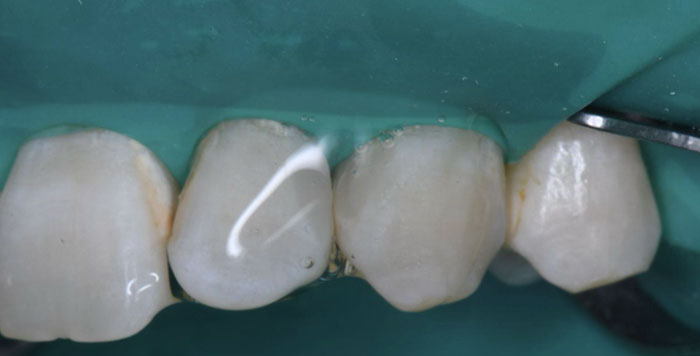

症例3:虫歯を治したい

治療前

治療後

治療中の様子

修復した最後に、酸素で阻害された表面(Oxygen Inhibitation Layer)を最終重合しています。

| 主訴 | 虫歯を治したい |

|---|---|

| 治療期間 | 1日 |

| 治療費 | ¥44,000×2歯(¥88,000) |

| 治療内容 | 象牙質まで達する隣接面の虫歯をラバーダム防湿下にて、コンポジットレジン修復を行いました。歯と歯が適切に接触するよう丁寧に処置を進めました。治療後の見分けがつかないくらい、綺麗に修復できました。 |

| 治療のリスク | 欠けたり、経年的な変色の可能性があります。 |